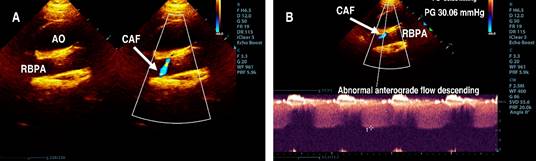

The parasternal short-axis view of the aortic root showed the right coronary artery (RCA) and left coronary artery (LCA) in their appropriate anatomical positions, with the proximal segment of the RCA exhibiting a Z score of 0.2 (Figure 1). However, the suprasternal longitudinal view identified an abnormal vascular structure with anterograde flow descending into the right branch of the pulmonary artery (RBPA) (Figure 2). The suprasternal short-axis view illustrated an anastomosis at the proximal segment of the RBPA, characterized by continuous, pulsatile flow, a maximum recorded velocity of 2.8 m/s, and a maximum gradient of 31 mmHg (Figure 3).

Figure 3: A) Suprasternal short-axis 2D color Doppler, the transducer tilted from anterior to posterior: view of abnormal anterograde flow descending into the proximal segment of RBPA (arrow). B) Suprasternal short-axis 2D with continuous Doppler: view of abnormal anterograde flow at the level of the proximal segment of RBPA with Vmax: 2.8 m/s.